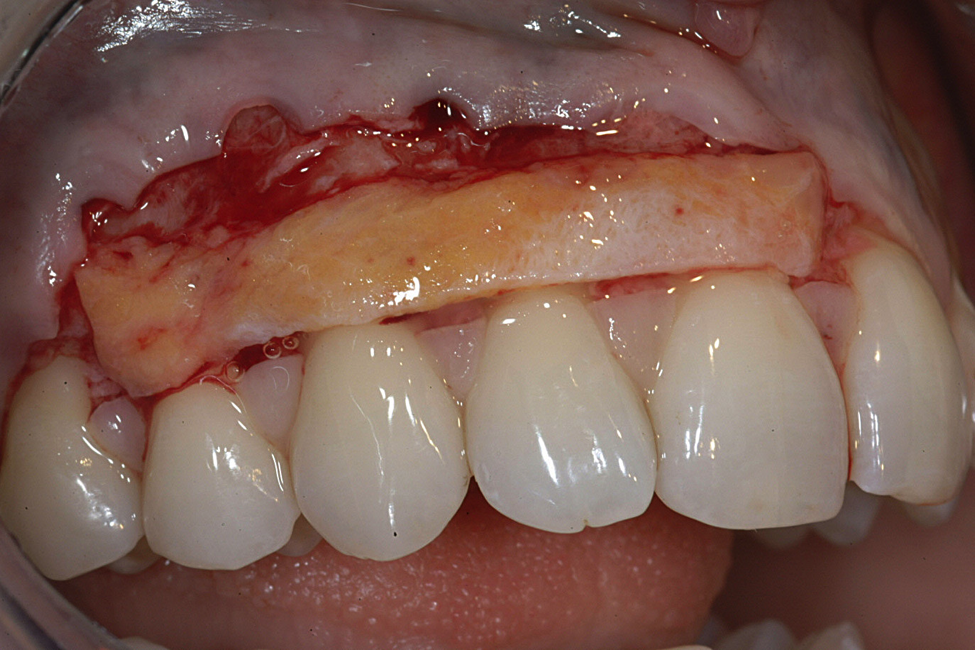

To procure a FGG, the tissue to be harvested is outlined using a #15C scalpel, then any rugae on the graft are smoothed off with a coarse #10 round diamond bur before removal of the graft (Figure 1). Smoothing the rugae reduces its appearance on the graft postoperatively for esthetic purposes and ensures equal thickness of the graft while it is being removed from the palate. Typically, a FGG is 1.5 mm to 2 mm thick. However, if more thickness is needed to try to gain root coverage, 2 mm to 2.5 mm can be harvested.18

The graft is undermined by making an incision into the connective tissue layer using a #15C scalpel, leaving the epithelial layer intact (Figure 2). The tissue can then be lifted away and freed from the palate (Figure 3), after which it can be trimmed as necessary and ultimately transplanted back to the patient. The palate is then covered with a positive-pressure stent worn by the patient continuously for 1 week postoperatively, except when cleaning the stent after eating. During the second week postoperatively, the patient wears the stent only when eating. The palate is expected to be fully healed after the second week and then no longer requires protection. Surgical dressing is placed on the graft recipient site to reduce postoperative discomfort and facilitate proper healing of the graft site.